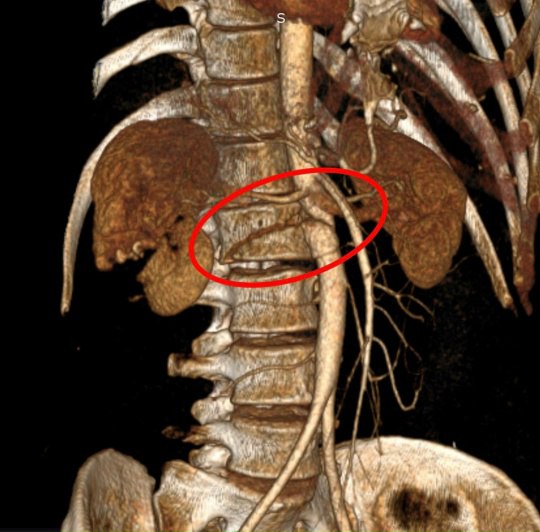

После госпитализации у пациента обнаружили массивную забрюшинную гематому, разрыв инфраренального отдела брюшной аорты, повреждение правой почки и поджелудочной железы.

Чтобы спасти человека, врачи провели экстренную операцию. Во время нее медики удалили почку с правой стороны, зашили разрыв брюшной аорты и перевязали поврежденные поясничные артерии.

Медики также обнаружили и устранили у пациента повреждения желчевыводящих путей. Из-за этого пострадавшему удалили желчны пузырь и провели дренирование холедоха. Затем пострадавшему потребовалась операция на позвоночнике с транспедикулярной фиксацией.